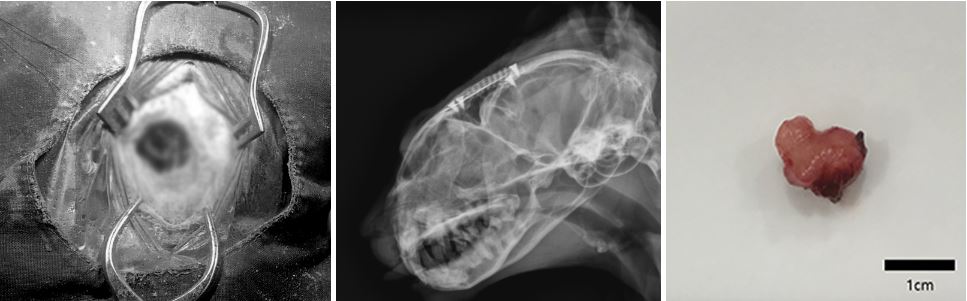

두개골을 열고 (Craniotomy - Partial transfrontal approach) 종괴가 주변 조직을 압박해서 생긴 낭종을 먼저 제거한 후, 정상 뇌조직이 손상되지 않도록 최대한 조심스럽게 종괴를 적출했습니다.

종괴를 제거한 후, 두개골 보호를 위해 티타늄 메쉬를 적용했습니다.

수술 일주일 후, 환묘는 수술 후유증 없이 잘 회복하여 퇴원했고, 조직 검사 결과 종괴는 예상대로 뇌수막종이었습니다.